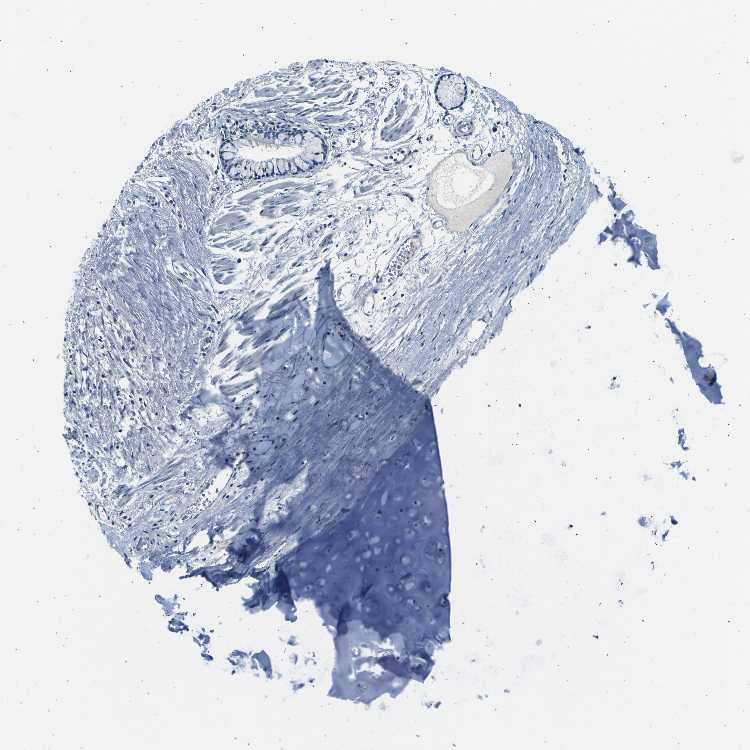

SOFT TISSUE 1 - Antibody stainingi

Antibody staining in the annotated cell types in the current human tissue is reported as not detected, low, medium, or high, based on conventional immunohistochemistry profiling in selected tissues. This score is based on the combination of the staining intensity and fraction of stained cells.

Each image is clickable and will lead to virtual microscopy that enables deeper exploration of all samples and also displays staining intensity scores, fraction scores and subcellular localization as well as patient and tissue information for each sample.

Antibody HPA012393

Chondrocytes Not detected

Fibroblasts Not detected

SOFT TISSUE 2 - Antibody stainingi

Peripheral nerve Not detected